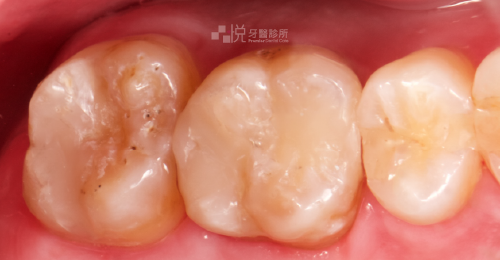

活髓保存術是牙齒因深度蛀牙、外傷等原因,導致內部牙髓組織快暴露與已暴露在外界時所做的治療,藉由良好的生醫材料,創造出保護神經的屏障,讓牙髓神經恢復健康,刺激牙本質的生成。

而當活髓保存術的牙齒常有結構上的缺損,建議搭配微創齒雕或假牙,保護牙齒避免斷裂、降低二度蛀牙的機率。